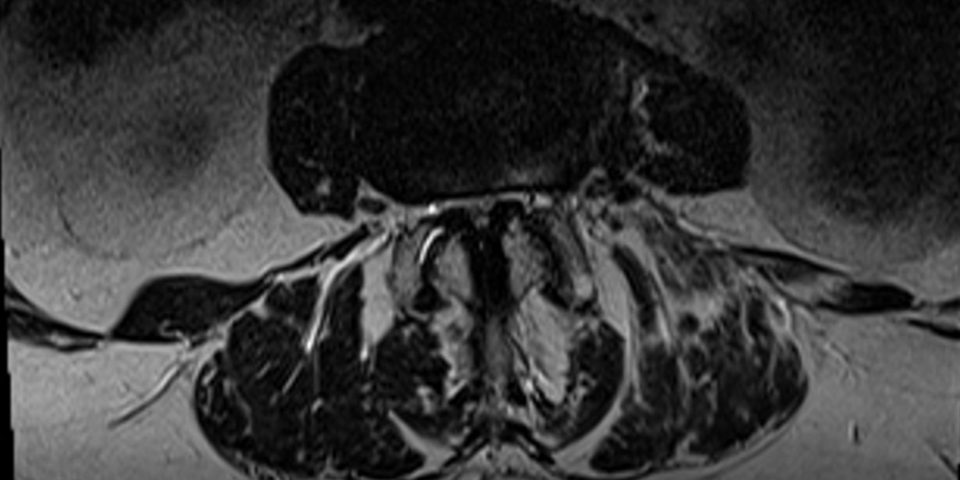

11.06.2019 – Prof. Ohnsorge zur Visite im NDR Am 11.06.2019 war Prof. PD Dr. Jörg Ohnsorge als Experte in der Fernsehsendung „Die Visite“ im NDR zum Thema Iliosakralgelenk (kurz ISG) zu Gast. Zuerst wurde im Beitrag über verschiedene Ursachen und die Wirkungsweise einer Blockade im ISG / Iliosakralgelenk oder Kreuz-Darmbein-Gelenk (Umgangssprachlich für das ISG)…